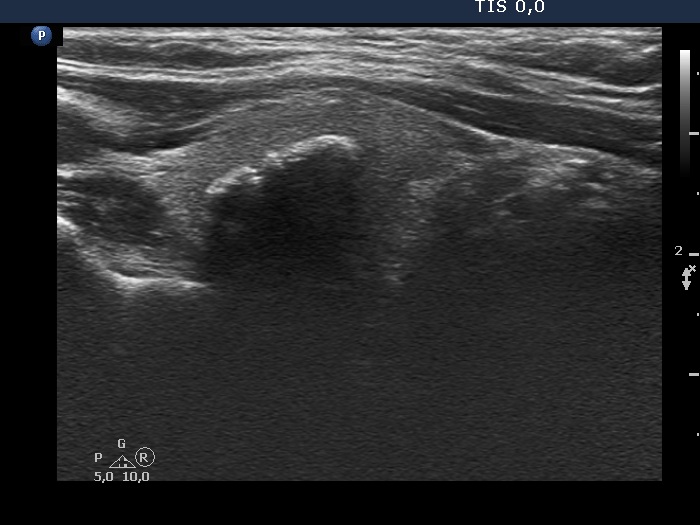

Ultrasonography. The thyroid was echonormal. There was a nodule presenting coarse calcification along its ventral surface. There was a spongiform-type cyst in the left lobe. The nodule has numerous echogenic figures most of them were caused clearly by posterior back wall enhancement.